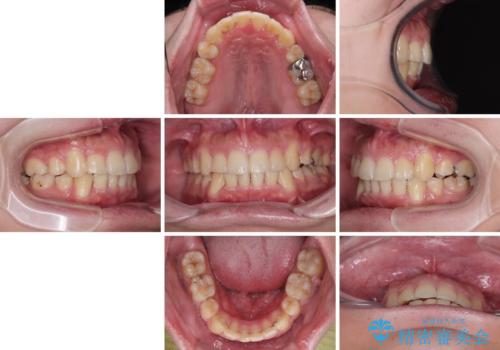

デコボコと口元の突出感を改善 抜歯矯正治療

- 八重歯を気にして来院された患者様です。

上下左右の犬歯が八重歯になっており、口元にもやや突出感があるため、上下左右の小臼歯4本を抜歯し、ワイヤー装置にて矯正治療を行うこととしました。

右上第一小臼歯は歯根癒着により移動せず、左上第二小臼歯は移動はするものの非常に動きが鈍かったため、抜歯したスペースを閉じるまでに非常に時間がかかってしまいました。

患者様には辛抱強く治療にお付き合いいただき、すっきりとした口元に仕上げることができました。